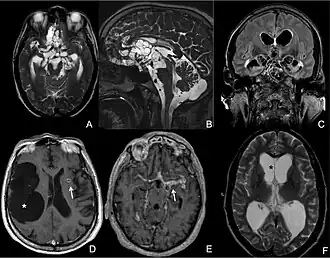

MRI of extraparenchymal neurocysticercosis

Different presentation patterns of extraparenchymal neurocysticercosis as revealed by brain MRI[36]